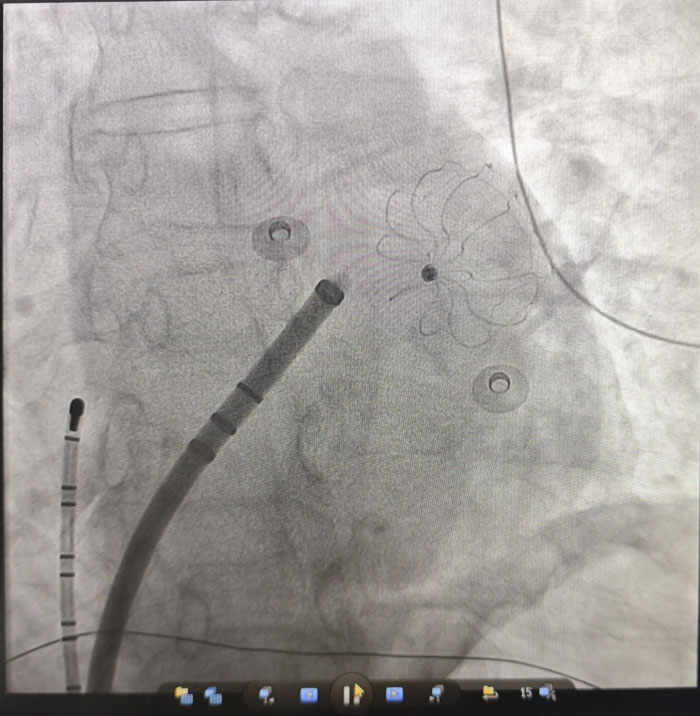

在房颤治疗方面,团队成功开展“房颤射频消融+左心耳封堵”一站式手术。患者为67岁女性,受房颤困扰多年,心悸、胸闷反复发作,生活质量严重下降,同时面临高卒中风险。传统房颤治疗通常需分别处理心律转复与抗凝问题,过程繁琐,对患者依从性要求较高。经全面评估与多学科讨论,团队决定采用微创介入技术,在一次操作中同步解决两大问题:射频消融精准定位并消除心脏内引发房颤的异常电信号,帮助恢复窦性心律,从根源上改善心慌、胸闷等症状;同时针对房颤患者约90%的血栓来源于左心耳的特点,植入封堵器封闭这一“血栓工厂”,从源头上预防脑卒中等血栓栓塞事件。

手术过程顺利,术后复查显示,患者心律已恢复为正常的窦性心律,左心耳封堵器位置良好、无残余分流。次日,患者即可下床活动,恢复迅速。该一站式诊疗方案,为高卒中风险、高出血风险,或无法耐受长期服药的房颤患者,提供了一次手术、双重获益的优质解决方案。